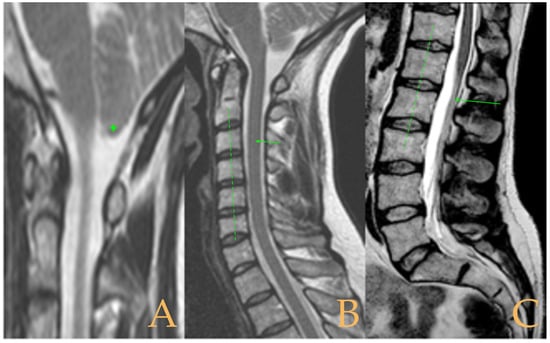

The MRI showed descent of the cerebellar tonsils, 13 mm pineal cyst, and multiple disc protrusions in T4-T8 and T9-T10, with herniation T5-T6. Straightening of the thoracic and lumbar spine. Low conus medullaris at the upper third level of the L2 vertebra (Figure 7). The full-spine X-rays showed a mild double-curved thoracic and lumbar scoliosis (<10° Cobb), and lower extremity dysmetria with shortening of the left lower extremity estimated to be 3 mm at the level of the acetabular roofs and 7 mm at the level of the iliac crests. Dextroconvex lumbar scoliosis was estimated to be 2°, and levoconvex cervicothoracic scoliosis was estimated to be 10° (both total, including all vertebrae). The estimated lateral curves, including all vertebral bodies in each region, were cervical lordosis 25°, thoracic kyphosis 34°, and lumbar lordosis 53°.

Figure 7. Imaging of patient 7. A: Descent of the cerebellar tonsils (star); B: straightening of the cervical spine (interrupted line) with image suggestive of medullar ischemia (arrow); and C: straightening of the upper part of the lumbar spine (interrupted line) and conus medullaris at the level of the upper third of L2 (arrow).